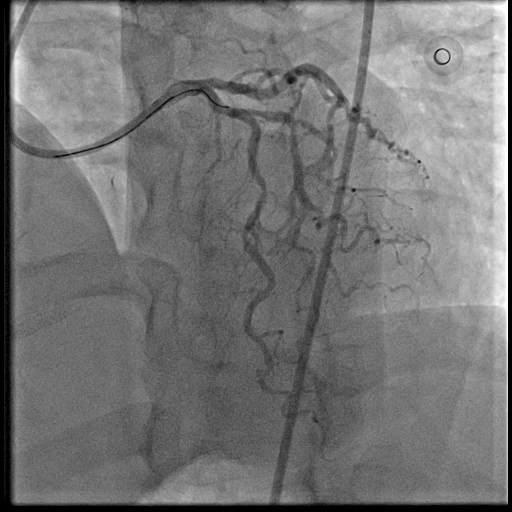

Coronary intervention was performed using an EBU 3.0, 6 Fr guiding catheter via the right radial artery approach. A Runthrough Floppy wire was advanced to the distal first LAD, and a Sion Blue wire to the second LAD. Pre-dilatation of the mid first LAD was performed using a semi-compliant (SC) 2.0 ¡¿ 15 mm balloon at high pressure. Intravascular ultrasound assessment revealed fibrocalcific plaque in both vessels. The vessel reference diameter of the first LAD measured 2.5 mm distally and 3.0mm proximally, with a minimal lumen area of 5.5–6.0 mm©÷ at the ostial segment. The second LAD had a vessel reference diameter of 2.5 mm distally and 2.75 mm proximally. Pre-dilatation of the second LAD was performed using a SC balloon at nominal pressure. Vessel preparation of the first LAD was then performed using a non-compliant (NC) 2.0 ¡¿ 10 mm balloon, followed by a scoring balloon(2.5 ¡¿ 15 mm) inflated at high pressure. The lesion was adequately prepared with minimal recoil and a type B non–flow-limiting dissection observed indicating adequate vessel preparation before DCB angioplasty. Two drug-coated balloons were inflated in the first and second LAD at nominal pressure for 45 seconds each. Similar non–flow-limiting type B dissections were observed in both LADs, with minimal recoil. Final angiographic results were satisfactory showing TIMI 3 flow with no immediate complications. The patient remained asymptomatic and discharged well the following day.

The favorable results achieved here reaffirm that with appropriate technique, imaging guidance and optimal lesion preparation, DCB-only PCI can serve as a viable and safe alternative to stenting even in anatomically complex scenarios such as dual LAD lesions with fibrocalcific disease. The absence of a permanent metallic scaffold preserves vessel physiology, reduces the risk of late stent thrombosis, and facilitates positive vascular remodeling over time. It reinforces the evolving paradigm shift toward stent-free revascularization in selected patients, particularly where dual vessel preservation and long-term vessel adaptability are desired.